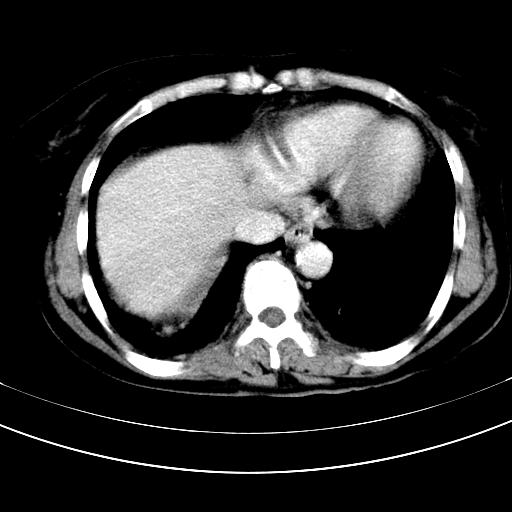

标题: CT12767:肝脏病变请会诊

补充强化片

胃内见充盈缺损,建议行胃镜病理检查,如果胃内无占位,则肝内考虑左叶、尾叶为包膜型肝癌,如有则考虑为转移瘤

胃内的充盈缺损,当时让患者俯卧位在扫描一下就 好了,当然最好是增强扫描,肝脏的病灶平扫很难定性,可以考虑是肝癌·血管瘤·转移瘤!

胃内见充盈缺损,建议行胃镜病理检查,如果胃内无占位,则肝内考虑左叶、尾叶为包膜型肝癌,如有则考虑为转移瘤,左侧肾上腺 明显增大,成结节改变,本人考虑转移瘤可能性大。

胃内的充盈缺损因胃壁不厚,我个人考虑为胃内残留物。肝左叶及尾叶病灶,我首先考虑血管瘤,其次为肝癌。(尾叶的更低密度区太规整)

胃内见充盈缺损,最好查胃镜

肝脏左叶和尾叶均见略低密度影,尾叶病变内见坏死?其边界清晰,形态规整1血管瘤,2肝癌待排

1.肝左叶及尾叶占位建议增强2.肝硬化

胃内充盈缺损考虑为胃内存留物,肝左叶和尾状叶两个病灶,均为低密度,建议增强。

胃内改变考虑存留物。

考虑:胃体小弯侧胃癌(或平滑肌瘤恶化或平滑肌肉瘤)伴肝转移,左侧肾上腺转移不除外.

胃内充盈缺损考虑为肿瘤,肝尾叶及左叶肿块考虑转移瘤

不强化不好说!肝内像是血管瘤,胃底考虑间质瘤。脾静脉还有曲张的可能。本病例必须强化明确!

胃窦部占位伴肝及左肾上腺转移可能大,建议增强扫描。

肝左叶及尾叶低密度灶,增强有渐进性明显强化,考虑血管瘤。胃内“充缺”首先要排除异物(食物),变换体位可鉴别。增强时机抓的不好,还应该有延时像。

谢谢楼主的增强片子,平扫没发现左侧肾上腺的问题很不好意思,可惜片子只有门脉期,所以还只有猜,肝脏的病灶在门脉期部分强化,首先考虑为血管瘤(其他的用一种病不好解释)胃要喝水就好了现在不好说是否有问题,左肾上腺的问题考虑是肿瘤。

做了增强后,可以明确胃是没有肿瘤的,肾上腺也没有肿瘤.肝左叶的病灶首先考虑血管瘤,应该再延迟,肝尾状叶的病灶仍不能排除肝癌的可能性.